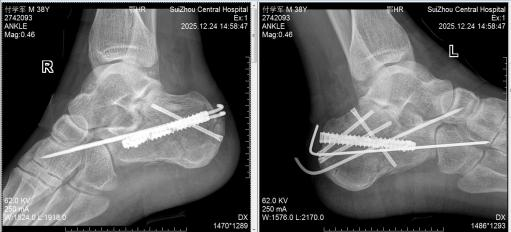

图1术前CT